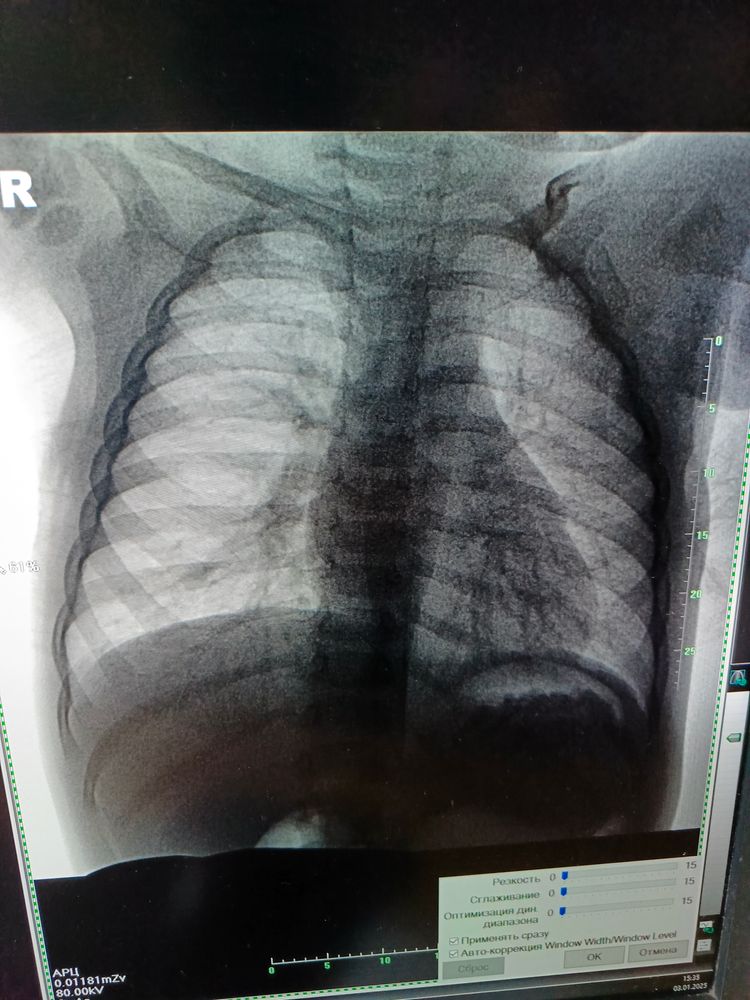

Девочки, добрый вечер, может кто разбирается в снимках? Дочке 1.5 , у нас мокрый кашель, сопли, расшифровка будет готова через несколько дней, я сфотографировала, может кто понимает?! Говорят пневмония или бронхит острый, температуры у нас нет